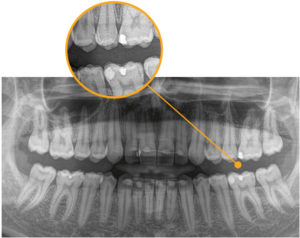

ついに当院も歯科用CTを導入しました!!

ドイツ シロナ社製の最新の歯科用CT「ORTHOPHOS SL 3D」です

他社のCTと比べると本当に画質が鮮明で綺麗です

CTの導入により、今までは2次元のレントゲン写真しか撮影できませんでしたが、これからは3次元のCTデータによる診断が可能になります

的確な診断ができることによってより質の高い歯科医療の提供が可能になります

インプラント治療においては補綴表示とインプラント計画の同時サポートで、新たなアプローチをもたらします。CERECでデザインされたクラウンとCT画像が融合され、一画面上に表示することができるソリューション。これにより、安全性が高くよりシンプルなプランニングが可能になります。3Dビューにより、患者さんへの治療計画の説明を画面を見せながらわかり易く行うことが可能になります

インプラント治療だけでなく埋伏歯(親知らず)の抜歯や歯根嚢胞また難治性の根管治療、歯根破折の診断や矯正治療、歯周病の治療などでもより正確な診断を可能にします